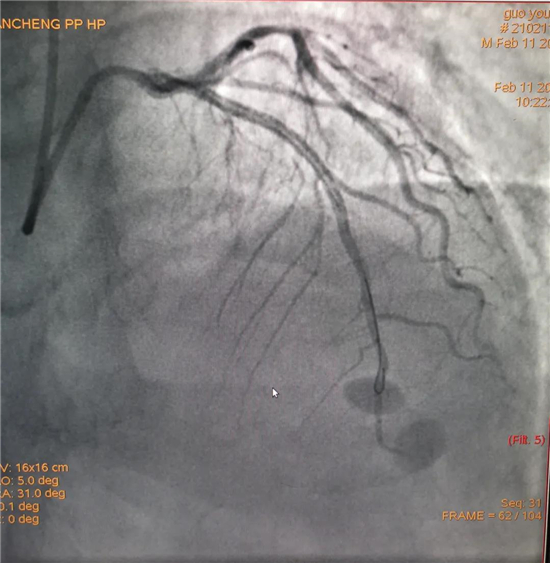

除夕,郭先生無明顯誘因突發(fā)胸痛,120急救人員到達現(xiàn)場,心電圖顯示:竇性心律完全性束支傳導阻滯。信息立刻發(fā)送到胸痛中心介入微信群中,心內(nèi)科值班醫(yī)生初步診斷為急性廣泛前壁心肌梗死,必須盡快進行急診支架治療,開通血管。值班醫(yī)生電話指導院前治療,并立即啟動胸痛綠色通道,24小時備班的介入治療團隊立即到位,9:30患者被送到導管室行冠脈介入診療,9:40急診PCI手術(shù)隨之開始,冠脈造影檢查提示左前降支閉塞,植入支架,堵塞的血管被順利打通,患者癥狀緩解,手術(shù)非常成功,10:20患者被送往病房進一步治療。